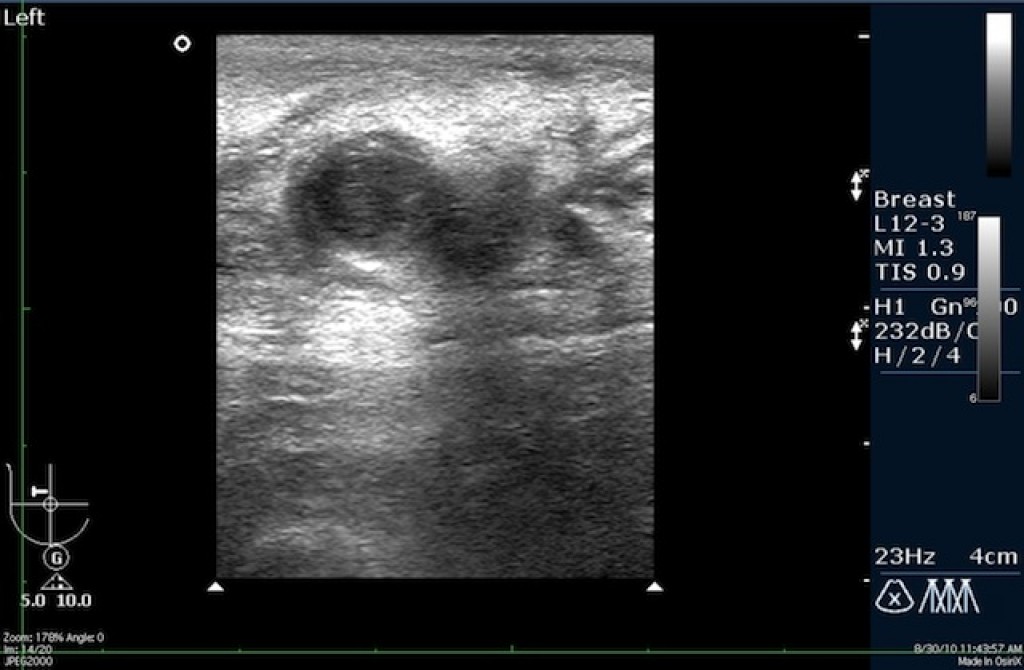

Узи молочной железы birads 3 123 фото